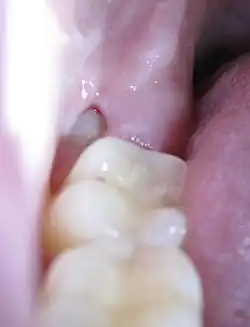

Een doorbrekende verstandskies 48 bij een 22-jarige vrouw

De meest voorkomende pathologie bij de verstandskies is de pericoronitis. Het is een ontsteking van het tandvlees rond de tandkroon van een nog niet volledig uitgekomen verstandskies. Het wordt gekenmerkt door pijn, een beperkte mondopening en slikklachten.